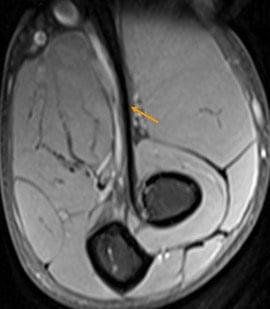

Elbow. Male, 31 years, acute pain and swelling after work out. Full-thickness tear of the distal biceps tendon. MR images showing retracted biceps tendon fibers (arrow) surrounded by edema. Note the thickened distal triceps tendon (asterisk) as a result of chronic overuse.

- Fluid-signal filled gap on STIR sequence, increased intratendinous signal intensity, and edema in the biceps muscle belly and surrounding soft tissues are characteristic for acute full thickness rupture.